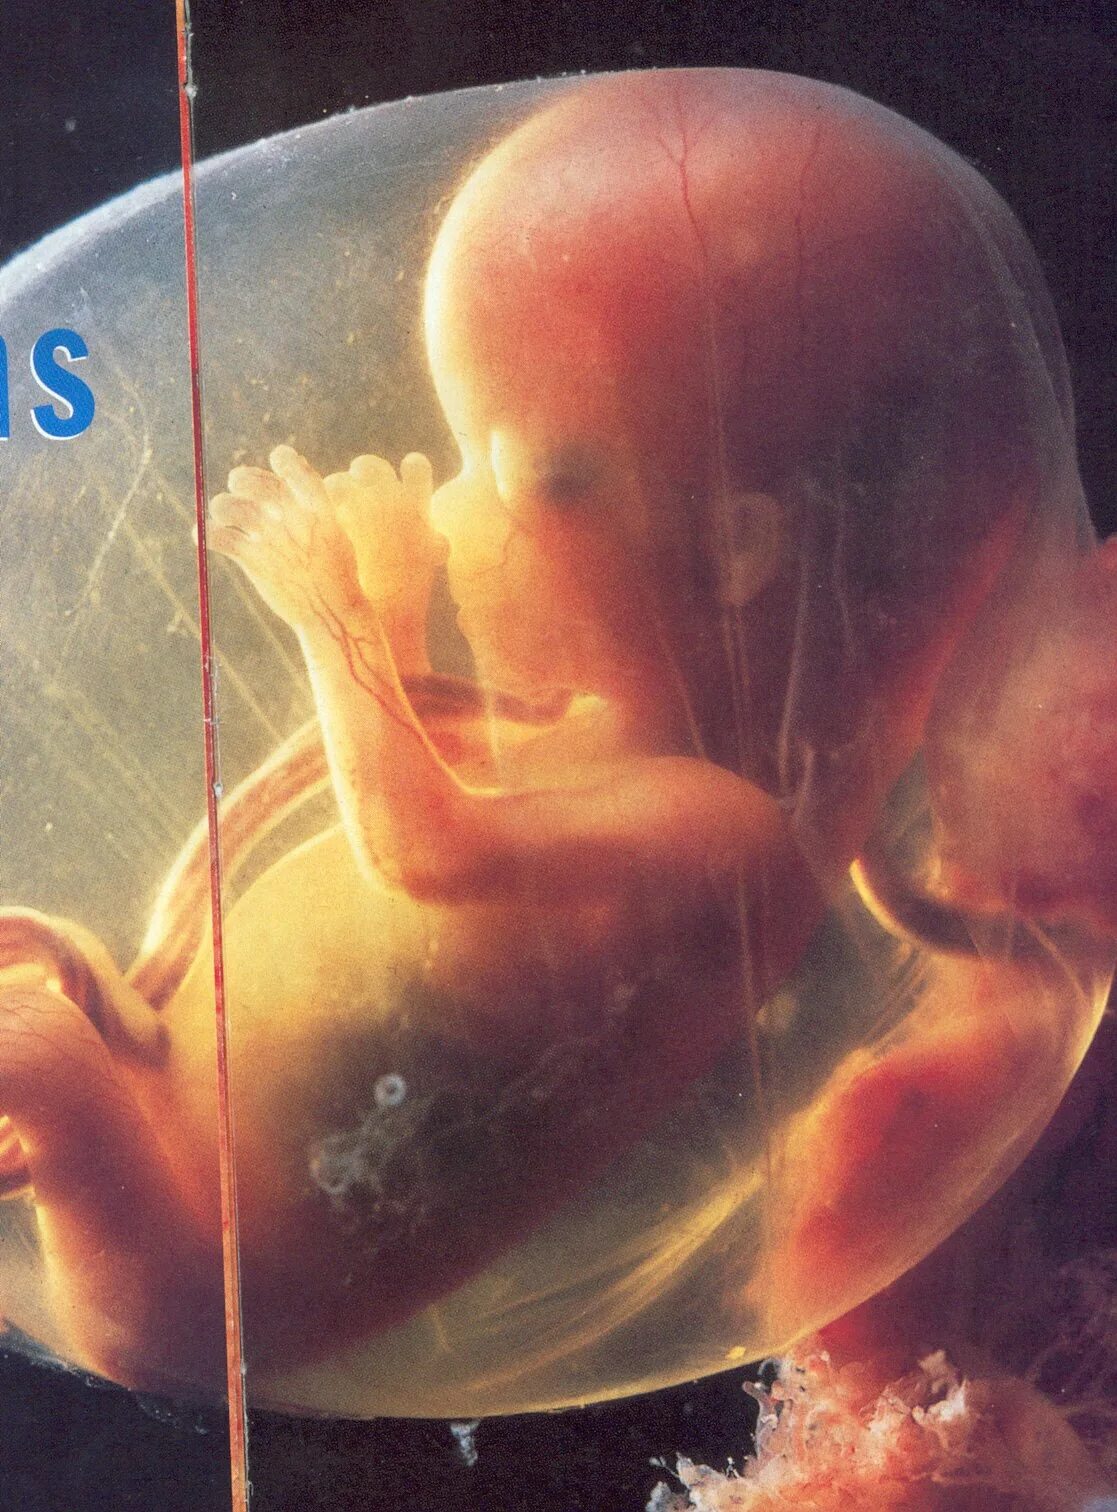

13 недель как выглядит малыш